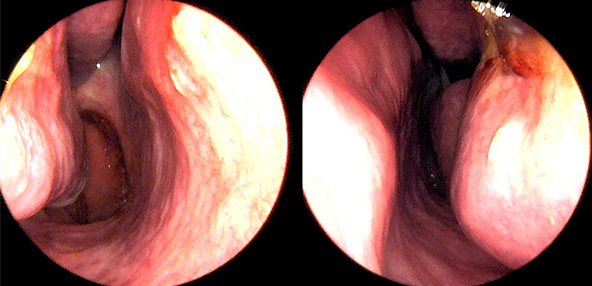

본 사진은 의료기관에서 진료를 본 환자이고, 전후 사진 인물이 동일인이며,동일조건에서 촬영이 되었습니다.